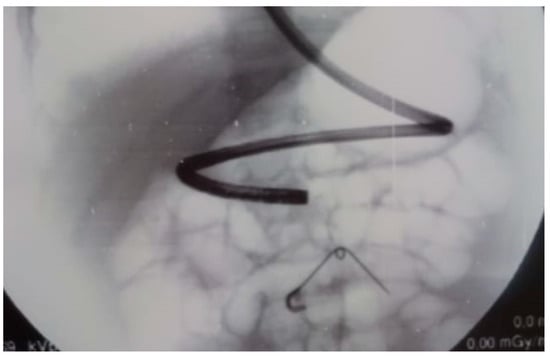

4. Endoscopic Retrograde Cholangiopancreatography (ERCP) and Laparoscopic Abdominal Surgery